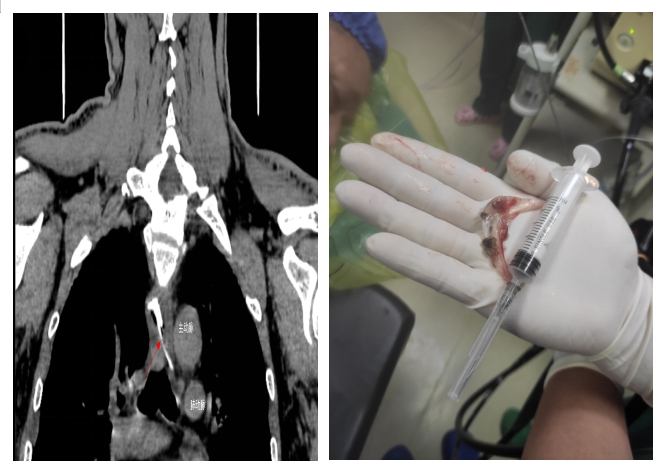

通訊員許欣報道:近日,衡陽市中心醫(yī)院心胸外科、消化內(nèi)科醫(yī)務(wù)人員在胃鏡下10分鐘取出刺穿食道的5×3厘米的魚頭骨,成功解除生命威脅。

當(dāng)日,黃先生在家中與家人聚餐時,不小心被魚頭骨卡住,強行吞咽多次,出現(xiàn)食管與胸骨中上段后部疼痛,火速到衡陽市中心醫(yī)院就診。接診醫(yī)師對患者進(jìn)行評估,嘗試經(jīng)喉鏡治療時,發(fā)現(xiàn)魚頭骨位置較深,行CT檢查發(fā)現(xiàn)魚頭骨卡于食管中段,穿破食管壁,與主動脈比鄰,非常危險,隨時威脅患者生命安全。隨即,患者被收治到心胸外科住院。入院后,廖金文主任一邊安慰,緩解患者的緊張情緒,一邊為其制定詳細(xì)的治療方案,計劃在手術(shù)室中嘗試胃鏡下取出魚刺。

在全身麻醉下,通過胃鏡,手術(shù)醫(yī)師清晰可見魚頭骨嵌頓部位為食管中上段。消化內(nèi)科副主任醫(yī)師劉昌智及主管護師羅雯娟攜手術(shù)室護理團隊,憑借豐富的臨床經(jīng)驗與技術(shù),10分鐘內(nèi)為患者實施了胃鏡取異物治療,成功取出魚頭骨,黃先生轉(zhuǎn)危為安。為防止意外,手術(shù)期間,心胸外科醫(yī)師在手術(shù)室全程守護。